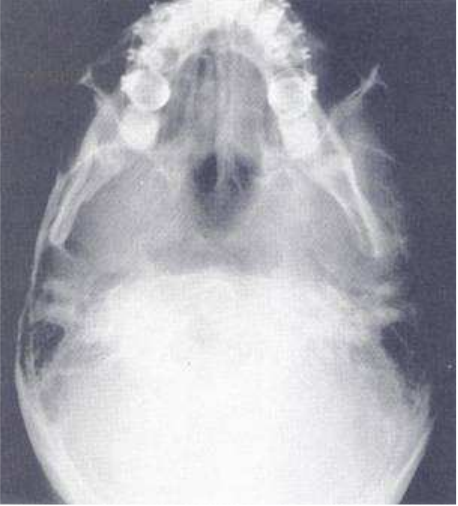

39.這張病人的CT scan顯示何處有骨折?

(A)右側顴骨骨體和左側下顎骨聯合 (B)右側上顎骨和左側下顎骨聯合 (C)左側顴骨骨體和右側下顎骨聯合 (D)左側上顎骨和右側下顎骨聯合